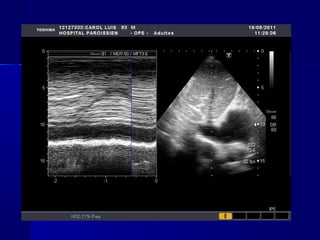

Hipotensión , normotensión, «hipertensión» Tipos de

Ecocardiográficos

SHOCK CARDIOGENICOSHOCK CARDIOGENICO

 ECOCARDIOGRAMA: de elección :

(motilidad parietal, función VI, VD, ruptura

cardíaca, CIV, infarto VD)

Hipotensión , normotensión,«hipertensión» Tipos de Shock Fisiopatología y manifestaciones clínicas y hallazgos Ecocardiográficos